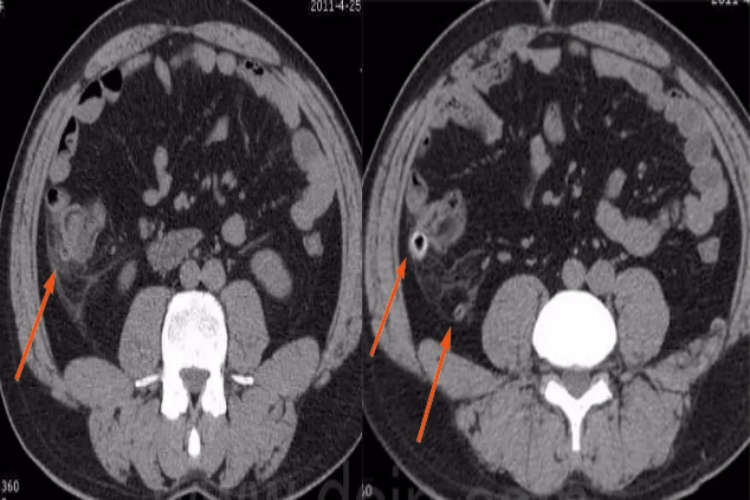

结肠憩室CT表现为结肠壁向肠腔外突出的囊袋状影,易发生于结肠带边缘系膜侧血管入肠壁处。单纯的结肠憩室一般没有症状,当合并憩室炎后,可呈持续性腹痛,出现恶心、呕吐症状。